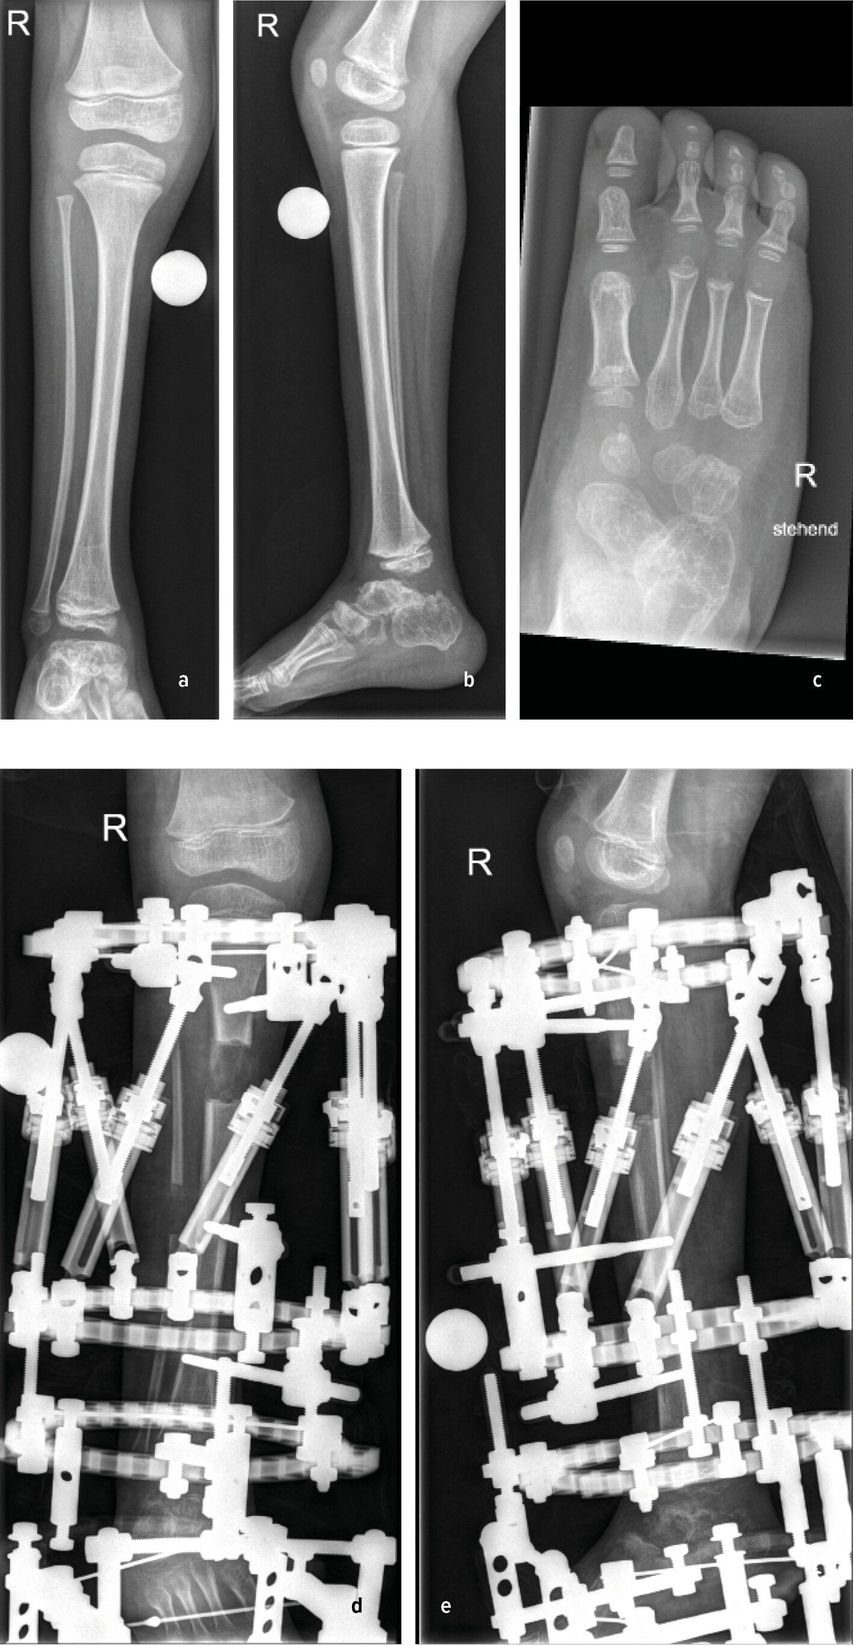

Die Biegung der Tibia richtet sich in diesem Fall nach vorne und zur Körpermitte. Diese Fehlstellung tritt vor allem bei Fibulahemimelie in unterschiedlicher Ausprägung auf. Die fibuläre Hemimelie tritt bei 1:50000 bis 1:135000 Geburten auf. Der Phänotyp der Fibulahemimelie reicht von leichter Verkürzung bis zu einem Fehlen der Fibula und führt dadurch zu einem typischen anterioren oder anteromedialen Bowing des Unterschenkels. Instabilitäten des Knie- und Sprunggelenkes können mit der Fibulahemimelie einhergehen.1,2 Fußfehlbildungen gekennzeichnet durch das Fehlen der lateralen Strahlen, Koalitionen, Equinovalgus- oder Klumpfußstellung können auftreten. Anschaulich illustriert wird dieses Zustandsbild durch den klinischen Fall eines 6-jährigen Patienten mit unilateraler FH und 4-strahligem Fuß rechts sowie einer ausgeprägten Beinlängendifferenz vor chirurgischer Rekonstruktion. (Abb.1a–c).3 Die sporadische Form ist meistens unilateral und kann mit einem kongenitalen Femurdefekt einhergehen.1,4 Bilaterale Formen sind selten und treten häufiger im Rahmen von Syndromen auf. Eine Disruption in der frühen Embryogenese wird als wahrscheinlichste Ursache einer Fibulahemimelie angesehen, die Ätiologie ist jedoch unklar.1 Die am häufigsten verwendete Klassifikation nach Achterman-Kalamchi unterteilt die Fibulahemimelie in lediglich zwei Typen mit einer Subgruppe:5

Abb. 1: 6-Jähriger mit unilateraler FH und 4-strahligem Fuß rechts sowie ausgeprägter Beinlängendifferenz vor chirurgischer Rekonstruktion (a–c). Laufende Valguskorrektur und Beinlängenausgleich mittels externen hexapoden Fixateurs mit Fußeinschluss

Die neuere Unterteilung nach Paley bezieht die Sprunggelenkspathologien in die Klassifikation mit ein (vier Typen mit Untergruppen) und gibt auch hier Empfehlung zu operativen Verfahren ab.1 Ziele der chirurgischen Rekonstruktion umfassen die Fußkorrektur mit plantigrader Position, den Ausgleich der Beinlängendifferenz bei Wachstumsabschluss sowie eine neutrale Beinachse. Neben konservativen Maßnahmen wie Schuhzurichtungen und Orthosenversorgung, erfolgt die Korrektur schließlich über chirurgische Verfahren wie Stabilisierungstechniken des Knie- und Sprunggelenkes, Wachstumslenkung sowie beinverlängernde Maßnahmen. Im Fall des 6-jährigen Patienten erfolgten eine Valguskorrektur und ein Beinlängenausgleich mittels externen hexapoden Fixateurs und Fußeinschluss (Abb.1d,e).6 In besonders schweren Fällen mit ausgeprägter Fehlbildung und Hypoplasie des Fußes kann eine Amputation mit anschließender Orthoprothesenversorgung in Betracht gezogen werden.7